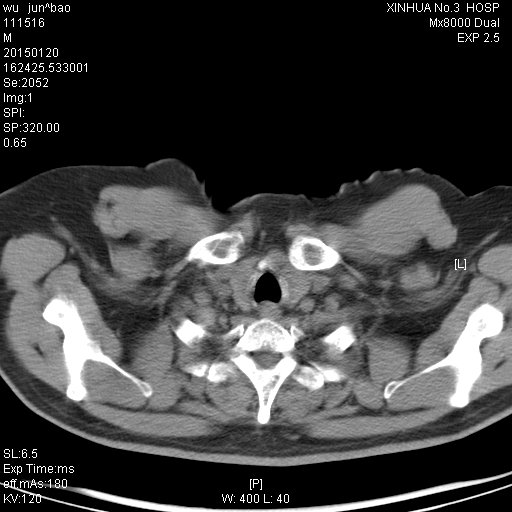

CT49791:何种肺部感染?请会诊

男,41岁,搬运工。咳嗽,咯血,低热。

这样的表现不像普通炎症与结核,像机遇性感染,住院病人的话先做个HIV检测看看,我见过几例这样表现的最后都是HIV阳性者,当然阴性也不能排除机遇性感染。